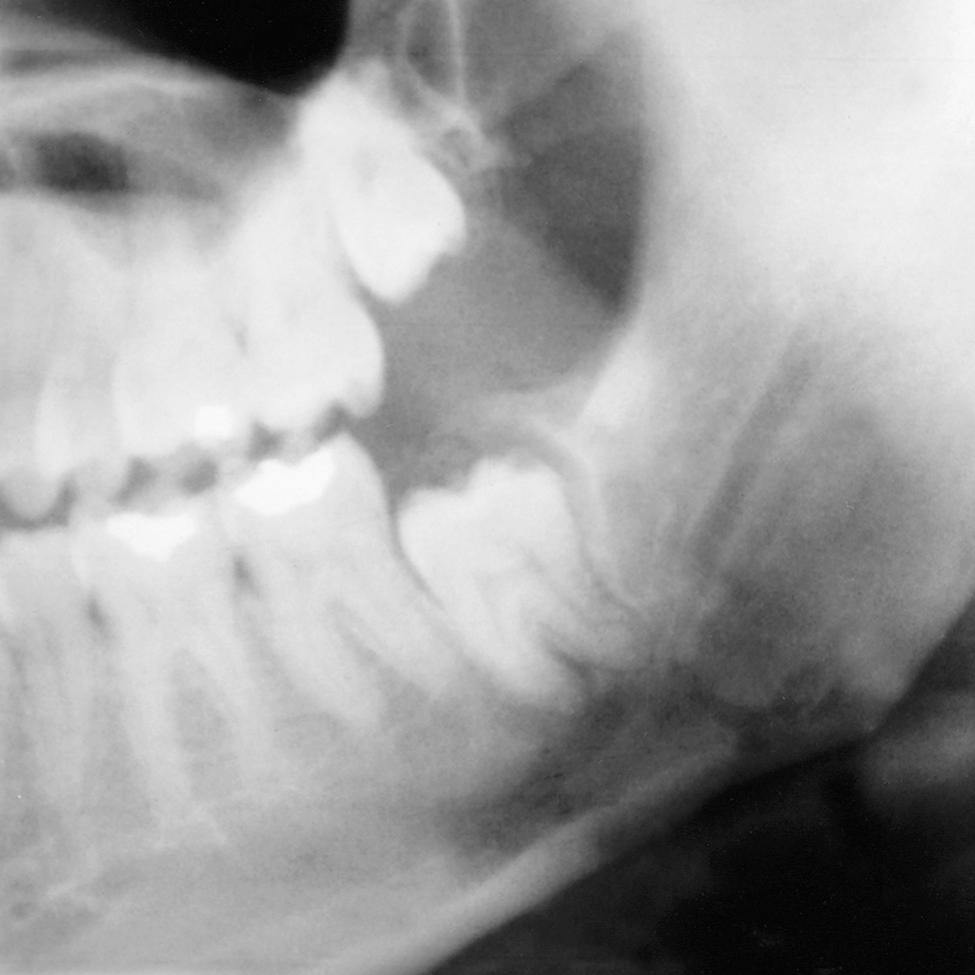

Occasionally an impacted tooth causes sufficient pressure on the root of an adjacent tooth to cause external root resorption ( Fig. 10.7 ). Although the process by which root resorption occurs is not well understood, it appears to be similar to the resorption process primary teeth undergo during the eruptive process of the succedaneous teeth. Removal of the impacted tooth may result in salvage of the adjacent tooth by cemental repair. Endodontic therapy may be required to save these teeth.

Fig. 10.7, (A) Root resorption of a second molar as result of an impacted third molar. (B) Root resorption of maxillary lateral incisors as a result of an impacted canine.